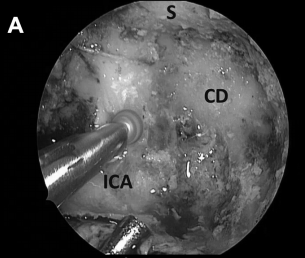

▼磨除骨质,暴露右侧斜坡旁的颈内动脉(ICA),注意血管保护(A)

神经内镜手术“动态控制”的重要关键优势是,它允许外科医生逐步靠近目标并放大术野,同时减少鼻腔内手术器械操作之间的冲突。这在某些情况下如重要神经组织的解剖分离、肿瘤暴露中至关重要的,例如在颈内动脉附近钻孔、暴露视神经顶部或在硬膜内分离解剖过程中。此过程类似于在执行更细致的操作时使用显微镜进行放大。例如,在手术操作系列图中,我们可以了解当从骨质解剖分离颈内动脉ICA(A)、从硬脑膜上解剖病变包膜(D)或耳蜗下的骨质时,神经内镜与磨钻头的距离有多近(I)。该技术结合了耳鼻喉科和神经外科手势的优点。